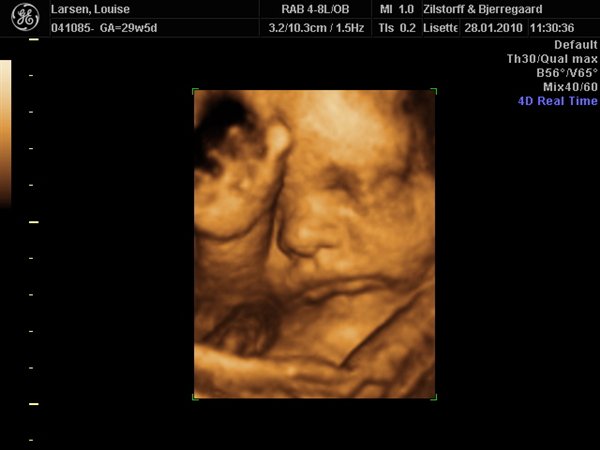

Vi har været til 3D/4D Scanning idag. Og sikke en vild oplevelse.... Har aldrig (udover min fødsel af Nicklas) prøvet noget så stort!

Her er lidt billeder: